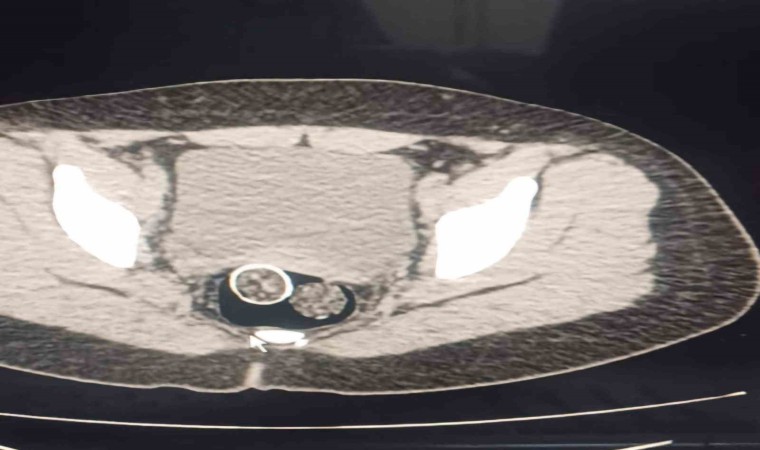

Denizli’de polisin düzenlediği uyuşturucu operasyonunda gözaltına alınan 5 şüpheliden 2’sinin yapılan iç beden muayenesinde rahim ve mideye saklanmış 320 gram uyuşturucu madde ele geçirildi.

Denizli İl Emniyet Müdürlüğü Narkotik Suçlarla Mücadele Şube Müdürlüğü ekiplerince, uyuşturucu ticaret yapan şahıs veya organizasyonların yakalanmasına yönelik operasyon düzenlendi. Düzenlenen eş zamanlı operasyonlarda 5 şüpheli şahıs yakalanırken, iki şahsın yaptırılan iç beden muayenesinde ve kullandıkları iki araçta yapılan incelemelerde rahimde ve midede uyuşturucu madde tespit edildi.